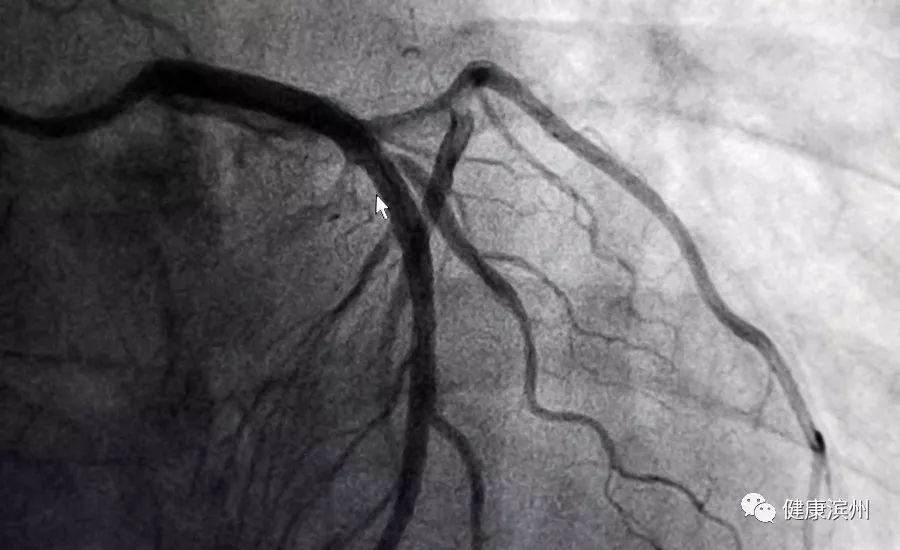

最后,让我们一起欣赏一下“妙手回春”的美丽“春色”。术前,光标指引处,左冠状动脉狭窄,严重影响了血流通畅。

术后,病灶消失的无影无踪,血管像航拍大地的河流,恢复了奔流不息的景象。